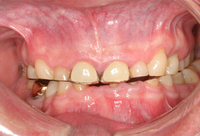

O desbastamento do esmalte dentário, fissuras e fraturas de dentes naturais em associação com atrito, abfração e abrasão devido à cerâmica

Da coleção do Dr. Alessandro Bracci